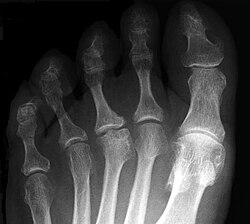

Der betroffene Vorfuß schmerzt bei Belastung, gelegentlich treten auch Schwellungen am Fußrücken im Bereich des Mittelfußköpfchens auf. Im Röntgenbild zeigen sich erst eine Veränderung in der Knochenstruktur des betroffenen Mittelfußköpfchens und erst später eine Abflachung und eine Verbreiterung (siehe Abbildung). Auf Dauer kann die Fehlform der Mittelfußköpfchens zu einer Arthrose führen.

| Morbus Köhler-Freiberg Freiberg disease 15 Y female | Eigenes Werk | Kinderradiologie Olgahospital Klinikum Stuttgart | Datei:Köhler II.jpeg | |